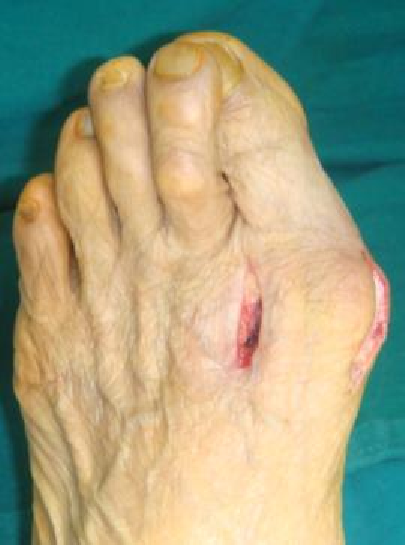

例4:罗XX,女,60Y。

左足:第1-5跖趾关节脱位,足拇外翻。

胼胝体:第一跖骨内侧,第2/3跖骨头跖侧,第5跖骨头跖/外侧。

左足:第2-5趾爪形趾。

右足:第4趾爪形趾,趾间关节胼胝,疼痛。

右足:第5跖骨头跖/外侧胼胝。

CT重建:第1跖骨头破坏。

术式:左足:第1跖趾关节融合+第2-5跖趾关节成形术;右足:第4趾间关节融合+第5跖趾关节成形术